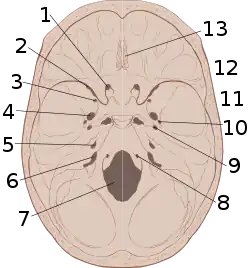

Non-contrast CT scan of a traumatic acute hematoma in the right fronto-temporal area. A diagram showing an epidural hematoma.

A diagram showing an epidural hematoma.